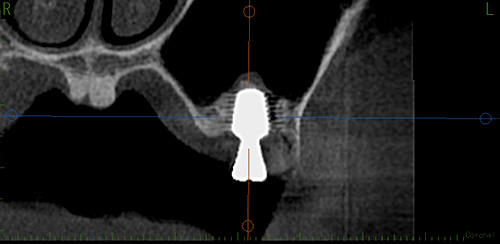

上の奥歯のインプラントではしばしば、歯がなくなり骨が薄くなってしまったことで、

そのままインプラントを入れると、その奥にある副鼻腔にインプラントが貫通する事故が起こってしまう可能性があります。

それを防ぐために、従来ではインプラント治療とは別に、骨を足すだけの手術を別におこなったり、歯茎を大きく切開して骨を足す必要があります。もちろんそれらを行うことで強い痛みや治療期間が半年以上かかったりしてしまいます。

当院では骨が薄い症例に対しても、副鼻腔を傷つけることなくインプラントと骨を同時にいれる手術が可能です。

これにより痛みが少なくなるだけでなく、治療期間も約3ヶ月と大幅に短縮することが可能です。

副鼻腔との距離が近くそのままインプラントをすると副鼻腔にインプラントが貫通し副鼻腔炎をひきおこしてしまいます。

通常なら歯茎の横から穴を大きくあけてサイナスリフトという方法で骨をつくり、半年程度待ってインプラントをいれますが、当院ではソケットリフトという方法で、歯茎の横でなく歯があるところから穴をあけ、ソケットリフトという方法で骨を入れそのままインプラントをいれます。

これによって痛みや腫れは最小限にすることができ、治療期間も半分以下の3ヶ月程度にすることができます。

ソケットリフトを入れた図